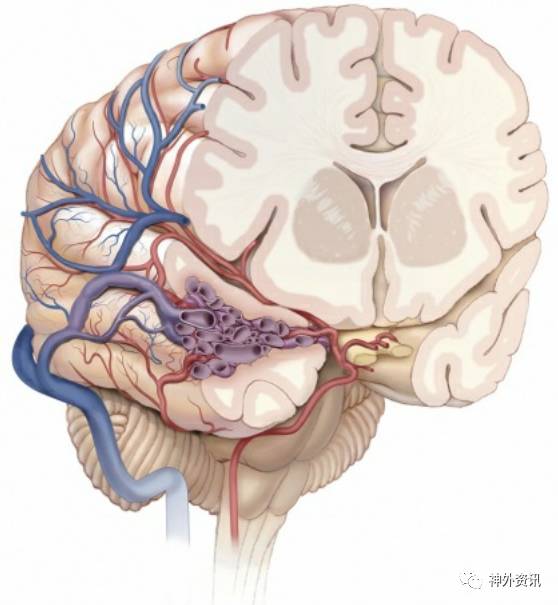

图1. MCA上干分支成为绝大多数侧裂和颞叶侧面AVMs的供血动脉(图谱来自于AL Rhoton, Jr)

图2. 颞叶内侧面和底面的显微手术解剖与AVMs手术相关。经过AVMs周围的血管需要与AVMs的供血动脉区分开来。P2段分支的命名不同作者叫法不一。(图片由AL Rhoton, Jr教授授权)